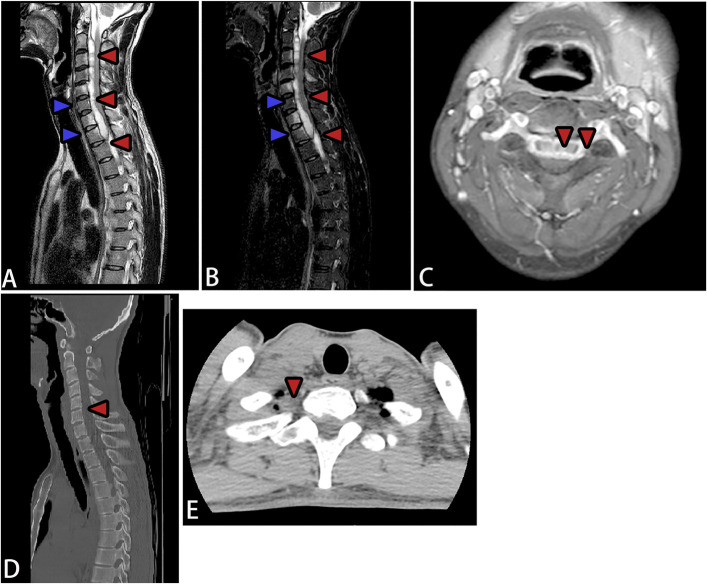

脊柱结核引起的脓肿通常发生在椎体的前部和外侧区域,常以冷脓肿的形式延伸至棘旁肌肉。虽然脊柱结核引起的椎管内脓肿很常见,但脊髓腹侧硬膜外腔纵向广泛脓肿的病例并没有很好的文献记载。该病的特点是发病隐匿,进展迅速,并具有不可逆转的神经损伤的高风险,突出了早期诊断和及时治疗的必要性。本文回顾了2例罕见的脊柱长节段结核性硬膜外脓肿,经过精确的手术干预和标准化的抗结核治疗,两例患者的症状均有显著改善。长节段结核性脊髓硬膜外脓肿(SEA)是一种非常罕见的并发症,可能导致严重的神经功能损害,磁共振成像显示广泛的脊髓硬膜外脓肿。临床表现,如颈部僵硬,容易被误认为结核性脑病;因此,建议使用增强MRI来鉴别SEA和结核性脑病。局部减压置管引流有助于保持神经功能,明确病因诊断,指导后续治疗。早期、充分和全面的抗结核治疗是成功管理的关键。

» Abscesses caused by spinal tuberculosis typically occur in the anterior and lateral regions of the vertebral bodies, often extending to the paraspinal muscles as cold abscesses. Although intraspinal abscesses due to spinal tuberculosis are very common, cases with longitudinally extensive abscesses in the ventral epidural space of the spinal cord are not well-documented. The disease is characterized by insidious onset, rapid progression, and a high risk of irreversible neurological damage, highlighting the necessity for early diagnosis and prompt treatment. » This review presents 2 rare cases of long-segment tuberculous spinal epidural abscesses, with both patients achieving significant symptom improvement after precise surgical intervention and standardized antituberculosis therapy. A long-segment tuberculous spinal epidural abscess (SEA) is an extremely rare complication that may cause severe neurological impairment, and magnetic resonance imaging revealed extensive spinal epidural abscesses. Clinical manifestations, such as neck stiffness, can easily be mistaken for tuberculous encephalopathy; therefore, contrast-enhanced MRI is recommended to differentiate a SEA from tuberculous encephalopathy. » Local decompression with catheter drainage can help preserve neurological function, establish a definitive etiological diagnosis, and guide subsequent treatment. Early, adequate, and comprehensive antituberculosis therapy is crucial for successful management.